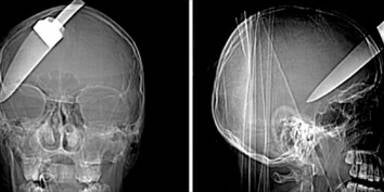

Es ist ein Wunder: Ein 16-jähriger Brite überlebte einen brutalen Angriff - ihm wurde ein Küchenmesser in den Kopf gerammt.

Einem 16-jährigen Teenager wurde ein fast 13 cm langes Küchenmesser in den Schädel gerammt, als er an einer Londoner Bushaltestelle einen Raubüberfall auf einen Bekannten verhindern wollte. Der junge Mann schritt zusammen mit zwei Kameraden beherzt ein - und wurde von den Dieben mit dem Messer attackiert. Ihm rammten sie das Messer in den Schädel, der zweite Bekannte erlitt eine Rückenverletzung, der Dritte wurde an der Schulter getroffen.

Der junge Mann überlebte die schwere Kopfverletzung nur, weil er sofort in ein Spital eingeliefert und einer Notoperation unterzogen wurde. Zehn Monate wurde er entlassen, und besuchte wieder die Schule.